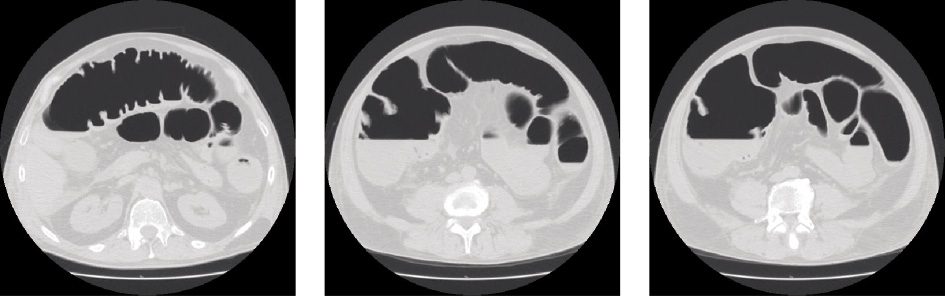

Viene, pertanto, sottoposto a Rx del torace e Rx addome (Figura 5), che conferma la marcata distensione meteorica delle anse enterocoliche, successivamente confermata dalla TC addome.

Figura 5. Rx torace tecnicamente limitato in urgenza. Ombra cardiaca affondata negli emidiaframmi. Non evidente falce di aria libera subfrenica. Marcata distensione meteorica delle anse enterocoliche

Dalla TC addome (Figura 6), eseguita successivamente, si riscontrano una sovradistensione enterocolica con multipli livelli idro-aerei, una sottile falda di versamento in corrispondenza della doccia parieto-colica di destra e di sinistra e anche nello scavo pelvico. Accessoriamente, si osserva una falda di versamento pleurico bilaterale con consensuale area disventilatoria bilaterale.

Figura 6. TC addome eseguita senza mdc ev, per alterata funzionalità renale. Non aria libera. Sovradistensione entero-colica con multipli livelli idroaerei. Sottile falda di versamento in corrispondenza della doccia parietocolica di destra e di sinistra e nello scavo pelvico. Ispessita la fascia lateroconale bilaterale. Imbibita la radice del mesentere. Per quanto dato valutare non alterazioni tomodensitometriche del parenchima epatico, pancreatico, splenico e renale. Accessoriamente si segnala falda di versamento pleurico bilaterale con consensuale area disventilatoria bilaterale